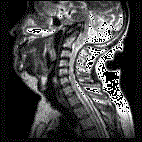

问题 根据图示考虑是何种疾病 ( )

选项 A、狭颅症 B、颅底陷入症 C、Dandy-Walker畸形 D、Arnold-Chiari畸形 E、中脑导水管狭窄

答案 B